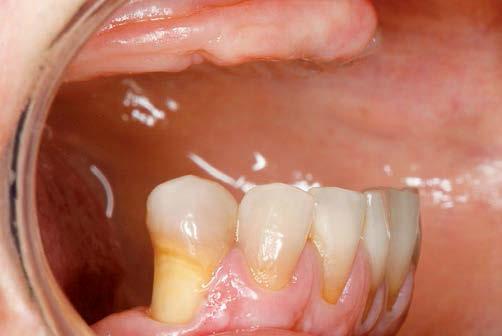

12

Después de casi sesenta años desde la introducción de las carillas, son muy pocos los desafíos clínicos que no pueden ser solucionados con los actuales sistemas restauradores de resina compuesta. La versatilidad y los resultados inmediatos son dos de sus grandes atractivos, y es por eso que las resinas compuestas siguen estando muy presentes en prácticamente todas las clínicas para poder restaurar los dientes anteriores y posteriores en diferentes grados de complejidad.

Capa de esmalte. (Capítulo 5. CarillasUnitarios).

Resultado final tras los procedimientos de acabado y pulido. (Capítulo 5. Carillas - Unitarios).